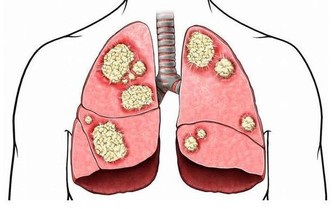

下蹲運動能夠治病強身的原理 人蹲下去,身體變成三折疊,被擠壓的血管收縮,氣血沖向全身未被擠壓的血管,迫使它們擴張、鼓起來;人一站起來,全身氣血又沖向原來被擠壓的血管,為它們灌滿血液;在這樣的一蹲一起、一壓一放、一沖一回的氣血往復運動中,就像涮瓶子一樣,使全身血管得到了反復沖洗,使血管軟化、加快血液迴圈和體內的新陳代謝、啟動免疫系統,增加了高密度膽固醇、靈敏了壓力感受器、把一些有害、有毒的代謝產物可迅速得以清除,人體自然就健康了。 下蹲可以激發經絡功能 雙腳是運行氣血、聯絡臟腑、溝通內外、貫穿上下的十二經絡的重要起止部位;加上奇經八脈,下蹲運動可以自然地激發這近20條經脈的經氣。 下蹲運動的其他作用和好處: ◇與長壽有關 對一些百歲健康老人的生活方式調查發現,他們從事田地耕作,蹲在池塘邊淘米、洗菜、洗衣服、廁所也是蹲的…這就強健了他們的腰腿,達到了祛病除疾的作用。 ◇強健關節和骨骼 下蹲可增強腰、髖、膝和踝關節的活動範圍,增強膝關節的靈活性,延緩關節的老化,關節如果活動少,會使骨骼變得脆弱,鈣就會流失到血液中,而且會積存在腎臟和膀胱中,造成排尿困難以及細菌繁殖等不良後果,所以經常使用和活動關節是永保年輕的關鍵。 ◇可以增強肌肉力量 常做下蹲運動可以增強肌肉力量,尤其是下肢的肌肉力量;兩條腿的力量增強了,可有效預防跌倒,走路時您會感到身體輕鬆,且生命充滿活力。 人體肌肉如果適度使用,將會更發達,但廢棄不用或過度使用就會退化。 ◇可改善血管功能 可以擴張微、小動脈血管,減少心臟外周阻力,可以改善微、小動脈血管壁的彈性,有效地降低血壓。 ◇可以降低血脂 下蹲運動通過刺激經絡系統,可使脾經運化功能增強,促進血管壁粥樣斑塊的分解,降低血液的粘稠度,減少血液中甘油三酯和低密度脂蛋白,增加高密度脂蛋白,促進脂代謝,進而改善血管的彈性,有效防治動脈粥樣硬化,對預防心、腦血管意外的發生有重要意義。 ◇可以促進新陳代謝 下蹲運動主要靠兩條腿的屈伸來支撐軀幹以上身體的重量;當下蹲時,身體的重量向下壓擠腿部肌肉中的血管,加快下肢的靜脈血液流向心臟;當身體起來時,解除了身體重量對下肢肌肉的擠壓,從心臟泵出來的動脈血快速進入下肢,如此反復下蹲、起來、再下蹲,有如「唧筒」的作用,加快血液迴圈和新陳代謝;血液迴圈加強了,回心血量增加,有效地改善心肌的血液供應和新陳代謝;血液迴圈加強了,胰腺等臟腑器官的營養與氧氣供應得到充分改善,胰島素分泌細胞的功能恢復正常,可有效地控制糖尿病。 ◇增強性功能對 下蹲運動可以強健大腿內側的肌肉,包括直接與性能力相關的長收肌,另外由於能使容易淤積在此的血液和淋巴液回流,也就促進了生殖器官的活躍,人到中年後性功能會逐漸減退,如果能長期堅持下蹲,性功能會逐漸提高。 ◇減肥效果明顯 下蹲能消耗很多熱量,可以減掉身上多餘的脂肪,特別臀部和大腿堆積的脂肪;另外下蹲時由於擠壓腹部,想知道自己一生愛情財運如何,添加大師微信:byou66 ,免費給你算命!促進腹腔臟器周圍的脂肪燃燒分解,減少脂肪的積累,亦可刺激胃腸的食物消化,促進消化酶的分泌。 ◇鍛煉可以使精神放鬆 可以暫且拋開煩惱、放下生活的壓力、使人的精神得到放鬆,調節情緒,增加生活樂趣,這對人的身心健康都有好處。 ◇能延緩大腦的衰退 如果腿衰老了(主要原因是肌肉、骨骼、關節的老化),大腦也會隨之衰老;腿衰老後人的活動減少,感官接受新資訊的機會減少,來自外界的刺激少了,大腦細胞也就不再活躍,人就會變得癡呆起來;下蹲可以加強腿的活動能力,增強和外界接觸,不但能夠延緩大腦的衰退,而且可以進一步增智開慧。 動作要領 下蹲的姿勢:正確的姿勢應該是從動作開始到結束,頭部到腰部的軀幹要始終保持筆直伸展的狀態,臀部要向身後撅起。 開始姿勢:要全身放鬆,兩腿分開,略比肩寬(或與肩同寬),自然地站立;腳尖的方向基本是倒八字形,以腳的第二趾的方向為准;下蹲時,膝蓋的方向要在第二趾的延長線上,這樣做起來比較自然而不吃力。 結尾姿勢:膝蓋彎曲,直到大腿與地而平行為止(視乎各人體力,老年人或初練者可先取用半蹲或1/4蹲);在完全蹲下時停頓片段最能鍛煉肌肉。 向上站起時的姿勢:向上站起時的要點是感覺整個腳掌在向下推壓地面,直立站起。 下蹲時的速度:1次下蹲的速度(時間)大致標準是5秒鐘1次(視乎體力,以舒適為佳),到了蹲的姿勢時,有意放慢速度更好。 呼吸方法:一邊下蹲,一邊吸氣;一邊站起來,一邊呼氣。 鍛煉的次數:注意量力而行,循序漸進,以1天做30次以上為宜;體弱的人開始少做,有體力的人可多做。 做下蹲運動的頻率:如果想維持健康或消耗脂肪的話,是應該每天鍛煉的。